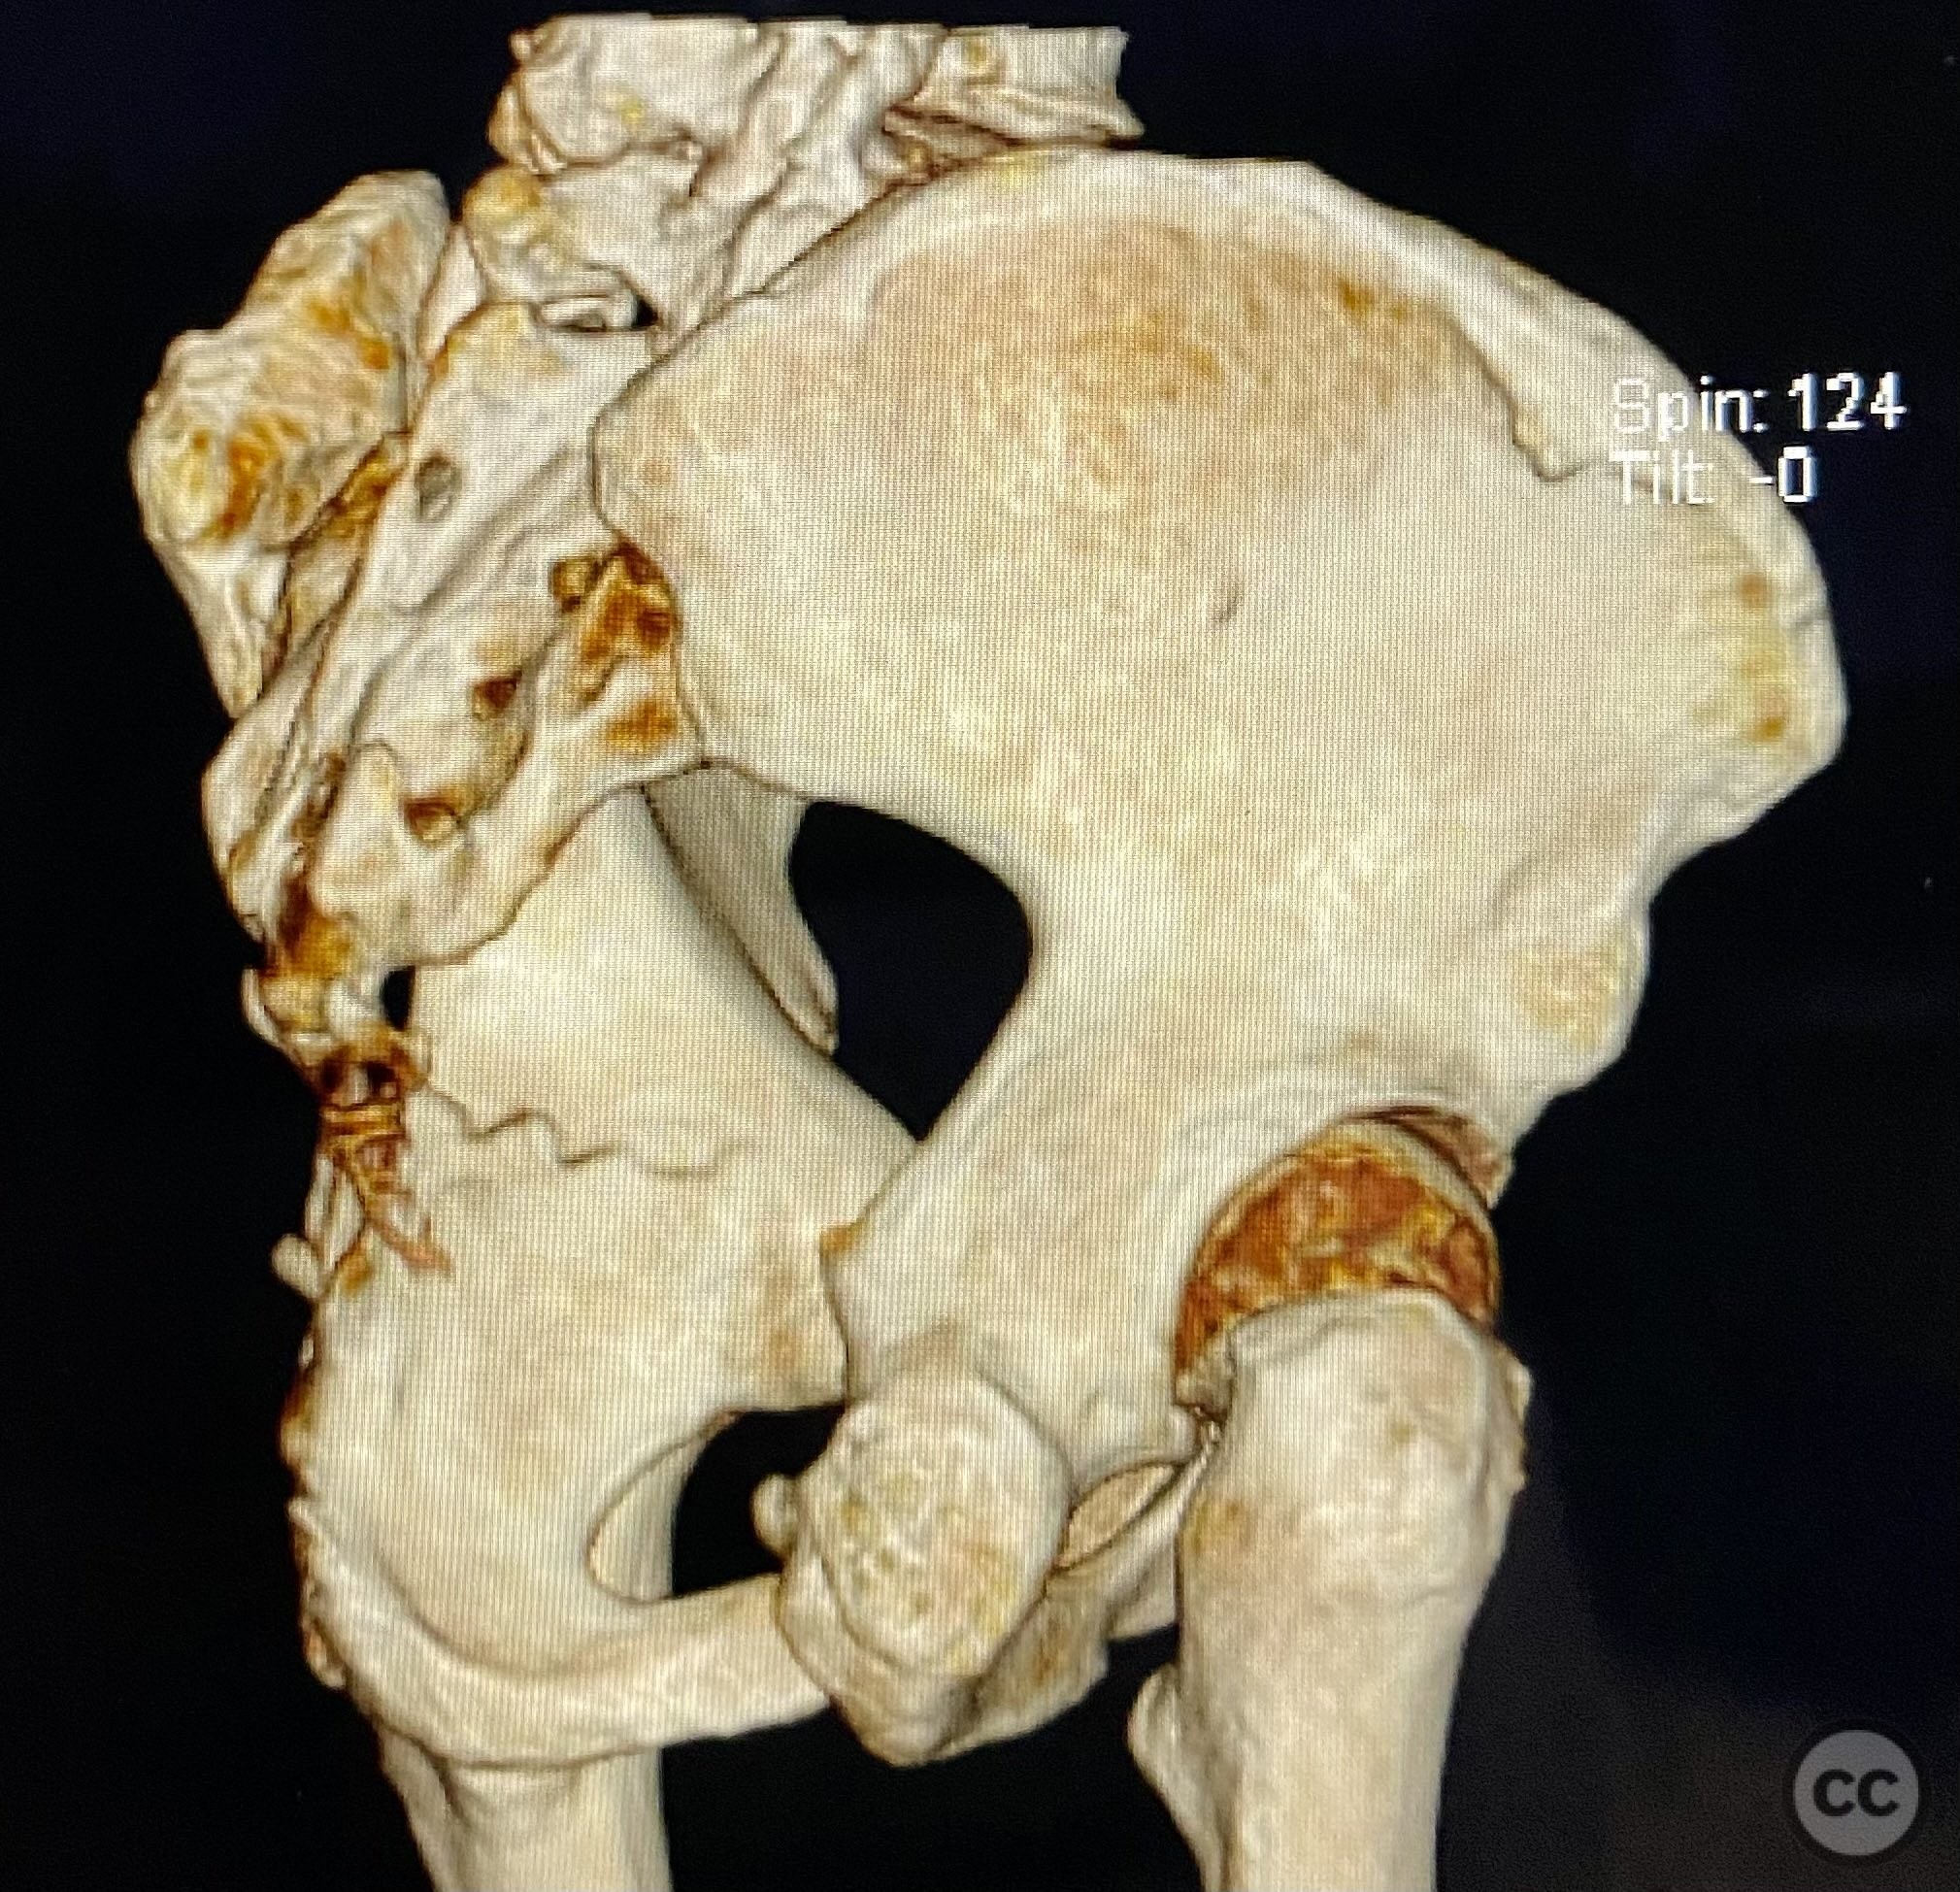

Clinical and radiological findings:  A patient sustained a posterior wall acetabular fracture-dislocation, characterized by comminution of the posterior wall, impaction of fragments into the posterior column region, and intra-articular loose fragments within the fossa acetabuli. Sagittal imaging demonstrated femoral head impalement on the intact wall, raising concern for potential irreducibility. Coronal and axial CT images revealed acetabular and femoral head impactions, peripheral wall comminution, incomplete fracture extension at the acetabular notch and quadrilateral surface, and an articular fragment within the joint. Surface renderings confirmed the extent of peripheral wall comminution and impaction. Despite these findings, a closed manipulative reduction was successfully achieved, resulting in a congruent reduction on post-reduction imaging.